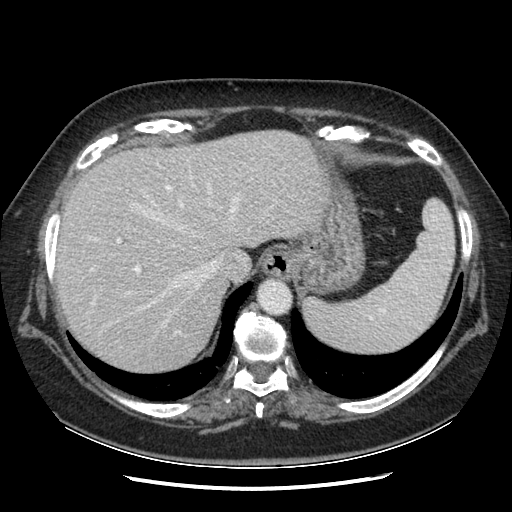

Image Grid

4×3 grid: Rows show different image types (Original NATIVE, Reconstructed NATIVE, Original VENOUS, Generated VENOUS), Columns show windowing techniques (No Window, Lung Window, Mediastinum Window)

Original VENOUS CT scan

Full window (WL 1023.5, WW 4095 → Low −1024, High +3071)

Actual HU range: [-160.0, 240.0]

Original VENOUS CT scan

Lung window (WL -600, WW 1500 → Low −1350, High +150)

Actual HU range: [-160.0, 150.0]

Generated VENOUS CT scan (A→B translation)

Full window (WL 1023.5, WW 4095 → Low −1024, High +3071)

Actual HU range: [-783.9, 601.6]